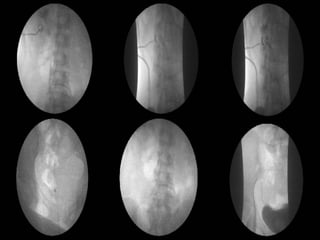

IVP and PV (Day 6) 5 min  15 min

1. Tear of L't renal pelvis or L't upper ureter with  extravasating  of contrast media out to L't retroperitoneal space. 2. L't hydronephrosis and hydroureter. 3. Intact of R't kidneys and its renal calyces, pelvis and R't ureter without dilatation or filling defect found. 4. Well distension of urinary bladder without filling defect found and minimal residual urine.

CT scan of abdomen (Day 6) 1. Tear of posterio-inferior wall of extra-renal portion of L't renal pelvis, with extravasating contrast media in L't peri-renal space. 2. L't hydronephrosis and L‘t hydroureter. 3. Post-partum enlarged uterus noted. Arrange L't Percutaneus nephrostomy (PCN) under the fluoroscopic guidance (after IVP study)